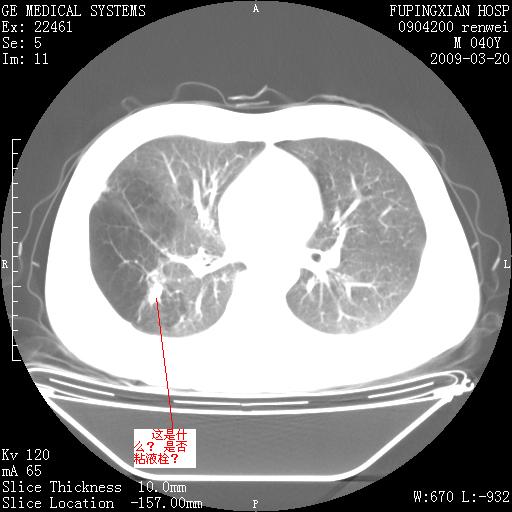

双肺弥漫磨玻样改变,肺纹理增重,考虑早期间质纤维化伴局部阻塞肺气肿,[考虑黏液栓]

右肺局限性肺气肿;[考虑黏液栓]所致。

右肺局限性肺气肿;[考虑黏液栓]所致

先天性支气管闭锁

右肺局限性肺气肿,原因?先天支气管闭锁?粘液栓?